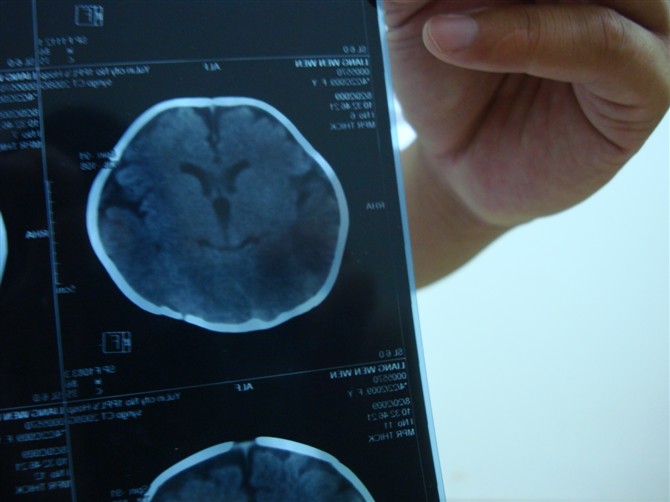

朋友的女儿,被玉林市第一人民医院医院诊断脑积水,各位老师帮忙看下!

顺产,无缺氧史,经常哭闹,无其它不适!

相机照的不太清楚,但还是请各位老师帮忙看下,谢谢!

胼胝体发育不良,外部性脑积水。脑白质密度减低,hie后遗症?

外部性脑积水,在第四军医大出版的《小儿ct诊断图谱中》诊断标准。书中列举四条标准:1。额顶部颅壁下间隙增宽在6-10mm;2。前纵裂增宽;3。脑室可增大或表现正常;4。属自限性疾病,1岁半以后可表现正常。 现在叫脑外间隙增宽 外部性脑积水国外文献又称其为 “假性脑积水”。临床可分为特发性外部性脑积水和继发性外部性脑积水。

图像不连续,外部性脑积水诊断问题不大,另外,三脑室上抬,侧脑室间距增宽,支持考虑胼胝体发育不良。